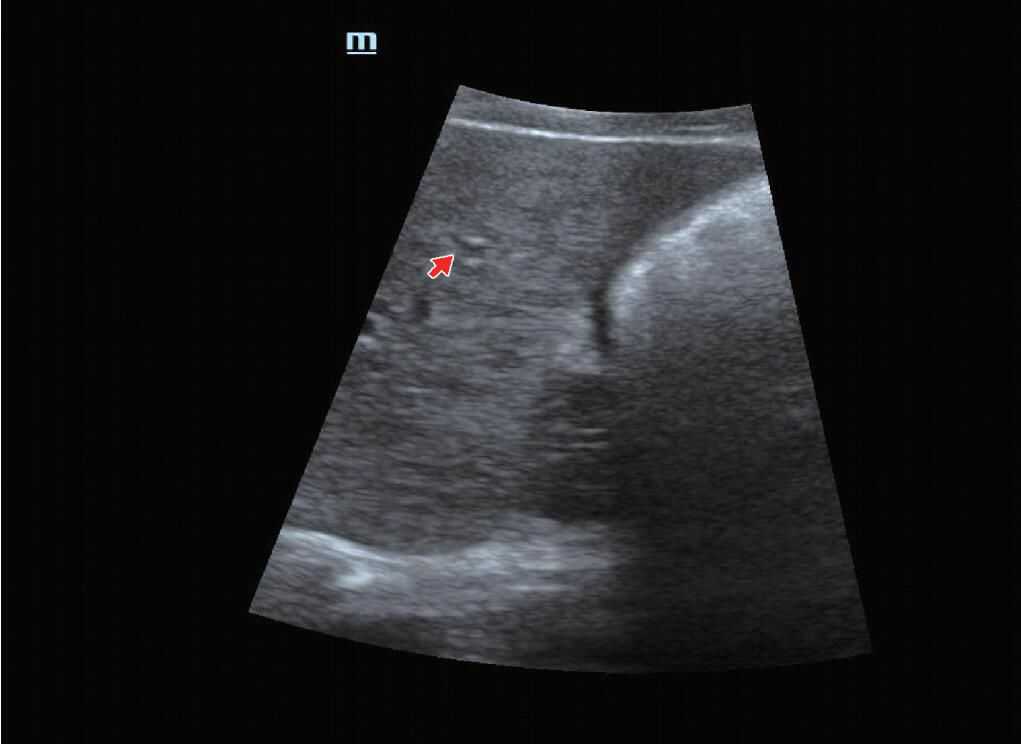

(4)部分容积效应:超声波形状特殊而且波束较宽,由超声断层扫描时断层较厚引起,例如:肝脏的小囊肿内可能表现为低回声(来自小囊肿旁的部分肝实质),或膀胱后壁因部分容积效应显示不清晰(图9)。

图9膀胱后壁因部分容积效应边缘显示不清晰